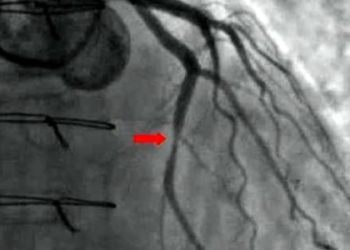

Optical coherence tomography-guided angioplasty reduces adverse events compared to angiography guidance

1. Major cardiac events were significantly lower in the OCT-guided group compared to the angiography-guided group. 2. Stroke, bleeding events, ...